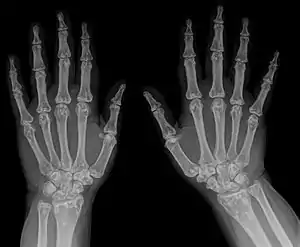

| Osteopoikilosis results in multiple enostoses. | |

An enostosis is a small area of compact bone within the cancellous bone.[1][2] They are commonly seen as an incidental finding on radiographs or CT scans. They are typically very small and do not cause any symptoms.[3] Their radiodensity is generally similar to cortical bone.[4] No treatment is necessary. Multiple enostoses are present in osteopoikilosis.[5]